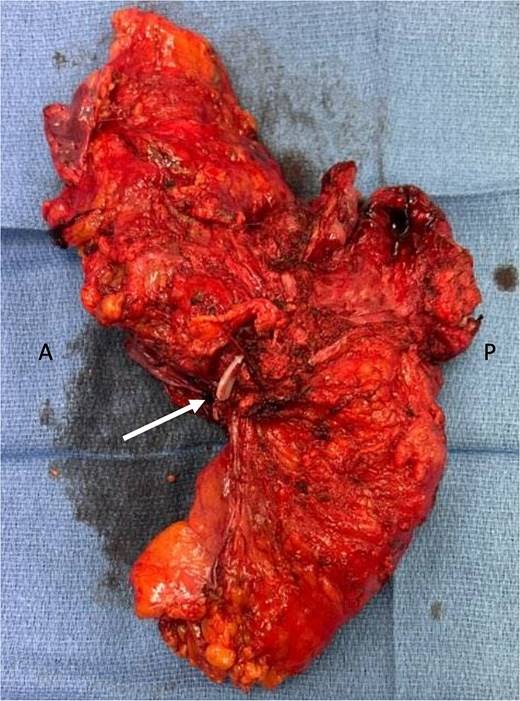

Genetic testing revealed a variant of unknown significance of the BARD1 gene. Post-treatment MRI showed yMR-T2 tumor. Sigmoidoscopy revealed a rectal ulcer, and she underwent robotic abdominoperineal resection (APR), cystectomy, and vaginectomy (Fig. 2). A uretero-sigmoid conduit and end colostomy were created. Final pathology revealed high-grade endometrial adenocarcinoma involving bladder wall, rectum, anus, vagina/cuff, and perirectal tissues. Negative for urothelial carcinoma, the original bladder biopsy was reexamined: staining GATA binding protein 3 (GATA-3) negative, PAX-8 positive, more consistent with endometrial origin. No rectal primary was identified, but two lymph nodes contained malignant cells with colorectal IHC features.

En-bloc resected specimen, right lateral view. Arrow indicates hemolok clip placed on ureter; letters A and P indicate anterior and posterior, respectively.